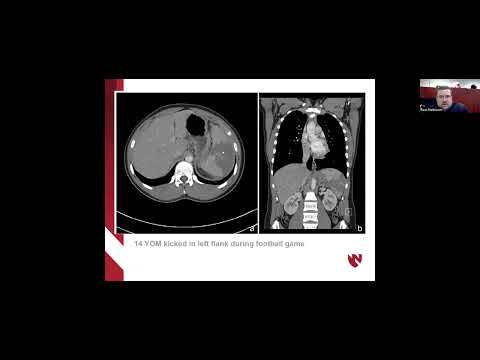

ICYMI, Dr. @rossmathiasen gave a presentation on Abdominal Injuries in Sports yesterday as part of the #FellowsLectureSeries.